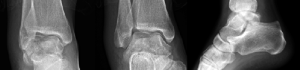

Case 1, Figure 3